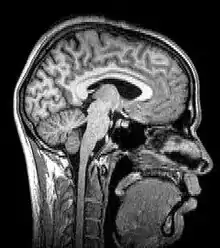

Tomography is imaging by sections or sectioning that uses any kind of penetrating wave. The method is used in radiology, archaeology, biology, atmospheric science, geophysics, oceanography, plasma physics, materials science, cosmochemistry, astrophysics, quantum information, and other areas of science. The word tomography is derived from Ancient Greek τόμος tomos, "slice, section" and γράφω graphō, "to write" or, in this context as well, "to describe." A device used in tomography is called a tomograph, while the image produced is a tomogram.

Although MRI (magnetic resonance imaging), optical coherence tomography and ultrasound are transmission methods, they typically do not require movement of the transmitter to acquire data from different directions. In MRI, both projections and higher spatial harmonics are sampled by applying spatially-varying magnetic fields; no moving parts are necessary to generate an image. On the other hand, since ultrasound and optical coherence tomography uses time-of-flight to spatially encode the received signal, it is not strictly a tomographic method and does not require multiple image acquisitions.

| Magnetic resonance imaging or nuclear magnetic resonance tomography | Nuclear magnetic moment | MRI or MRT | |